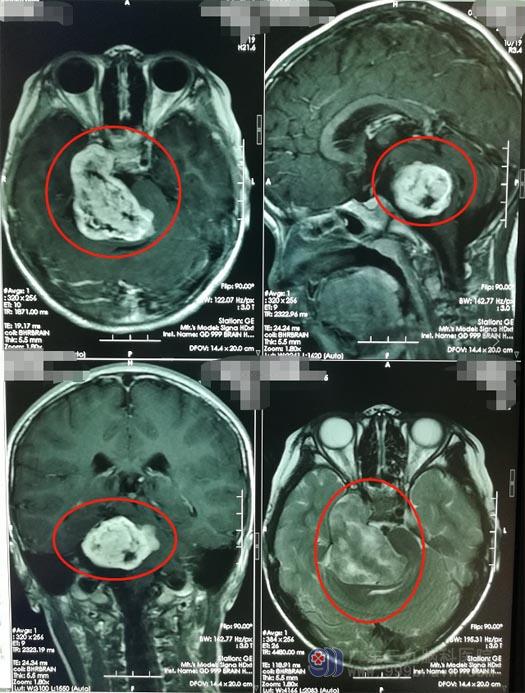

在广东三九脑科医院进一步影像检查后,诊断:右侧中后颅窝巨大三叉神经鞘瘤。

完善术前检查后,鲁明带领神经外五科治疗团队在全麻下为小萱行“右侧中后颅窝巨大三叉神经鞘瘤切除术”。术中见肿瘤起源并明显压迫三叉神经,将肿瘤顺利全切,面听神经、后组神经等保护良好,Labble静脉等引流静脉保护良好。